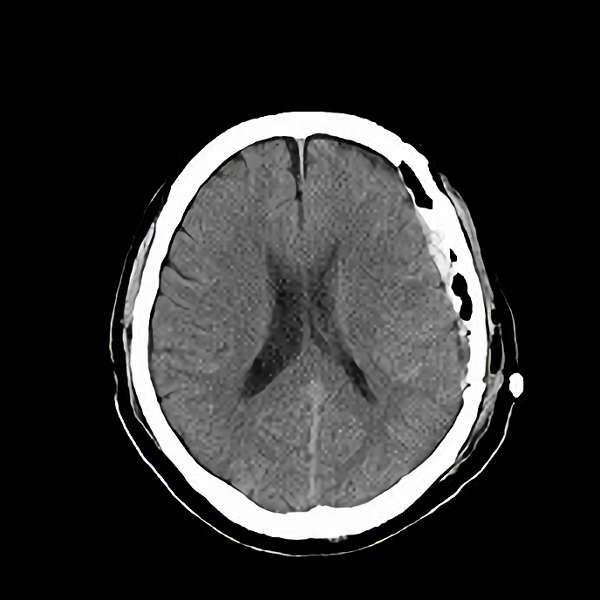

No.359 モニタリング

No.359 手術前

No.359 手術中

No.359 手術後

出血既往があり。2回の手術前血管内手術の後に、

Lateral transpeduncular approachにより再々出血予防を目的に

摘出手術を行う。完全摘出であることを確認した。

手術による合併症や後遺症なしで退院した。経過良好。